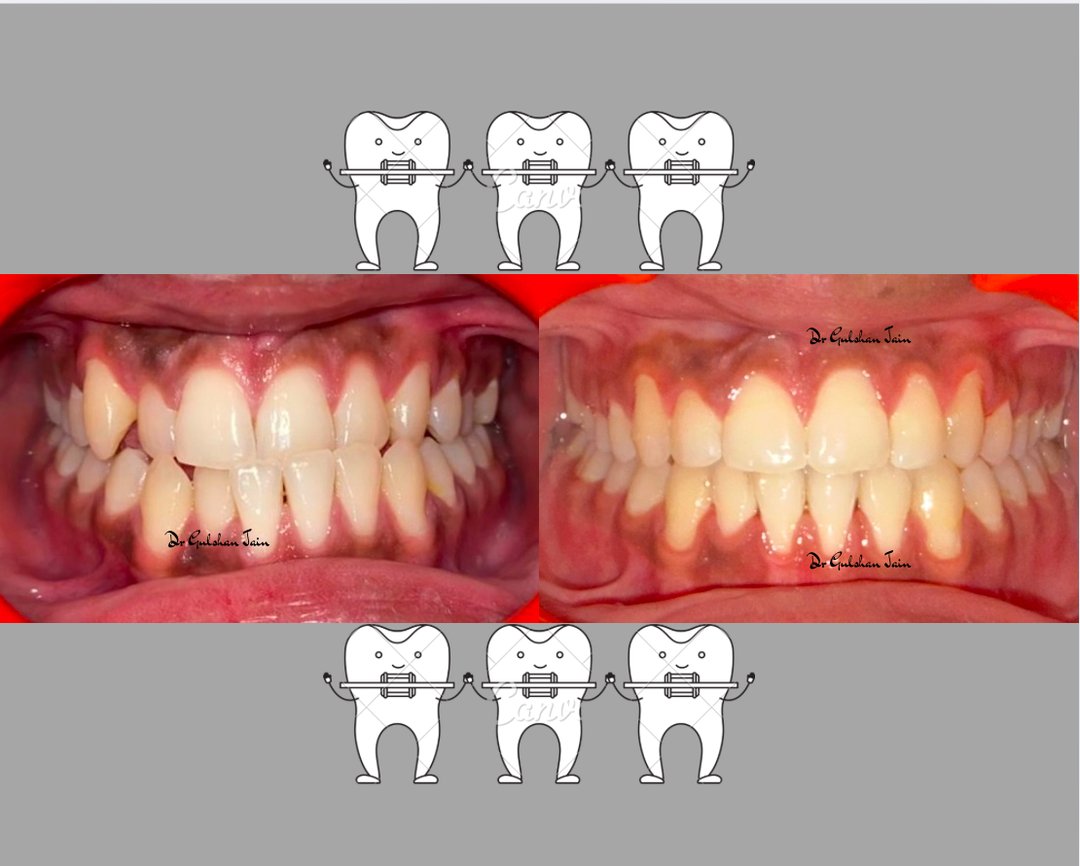

Welcome to our gallery

See how our company transforms ideas into reality. This gallery is a visual testament to our work and achievements.